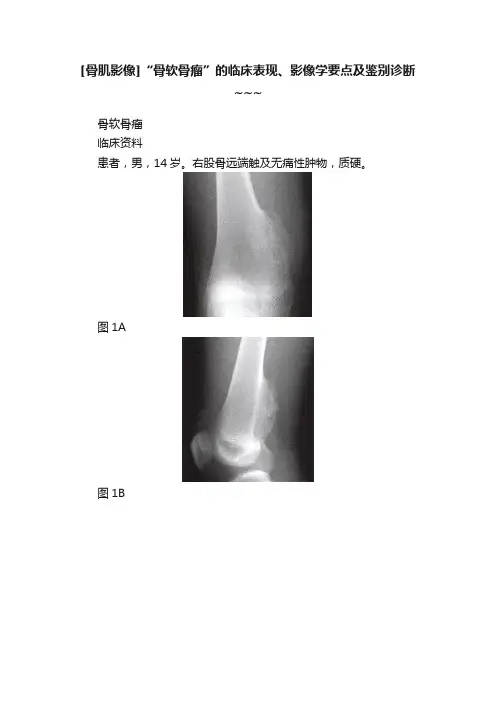

[骨肌影像]“骨软骨瘤”的临床表现、影像学要点及鉴别诊断~~~骨软骨瘤临床资料患者,男,14岁。

右股骨远端触及无痛性肿物,质硬。

图1A图1B图1C图1D图1E图1F影像学报告描述右股骨远端正、侧位(图1A、图1B),右股骨远侧干骺端内侧宽基底骨性突起,其皮质及髓腔与母骨相延续。